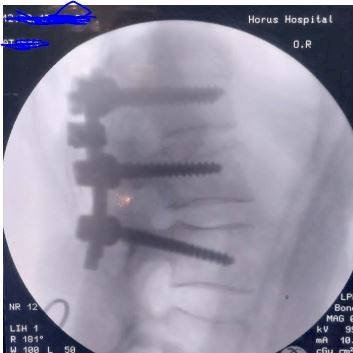

فى اليوم التالي تم عمل لسته عمليات جراحيه ما بين الجراحات المتقدمة لتثبيت الفقرات القطنية و بعدها تم عمل مناظر مخي استكشافي لبطينات طفله بالغه من العمر ١٤ يوم تعانى من استسقاء مستعصي ببطينات المخ وتم لها كى لضفيره الشعيرات الدموية المخية وفك التصاقات بطينات المخ.

اليوم التالي تم اجراء جراحه دقيقه لمريض يعانى من خذل نصفى بالطرفين السفلين ناتج عن اشتباه ورم ثانوي بالفقرات الصدرية ضاغط على الحبل الشوكي وتم اجراء جراحه دقيقه لتوسيع القناه العصبية الصدرية و اخذ عينه من الورم للتحليل؛ على الفور بعد الاجراء تحسن الخذل الموجود لدى المريض والنتيجة كانت مرضيه تماما للمريض.